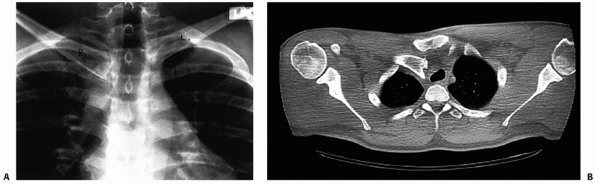

![]() |

FIGURE 40-12 A. Routine anteroposterior radiograph of posteriorly dislocated right SC joint. B.

The anteroposterior view is suggestive of a posterior dislocation. However, the CT scan clearly demonstrates the posteriorly displaced right medial clavicle. Note the displacement of the trachea. |

It clearly distinguishes injuries of the joint from fractures of the

medial clavicle and defines minor subluxations of the joint. One must

remember to request CT scans of both SC joints and the medial half of both clavicles

so the injured side can be compared with the normal side. Numerous

authors have reported on the value of using a CT scan as the method of